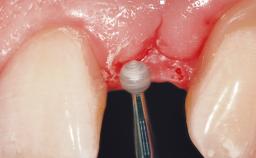

Immediate Placement of an Implant in a Maxillary Left Central Incisor Site

A 33-year-old female patient presented with an upper left central incisor that required extraction after a failed endodontic therapy. The tooth had been traumatized when the patient was a teenager and had undergone several endodontic treatments, including two apicectomy procedures. The patient was in good health and did not smoke. Clinical examination showed that the patient had a high lip line. In full smile, the gingival margins of the upper teeth were visible to the first molars. The gingival margins of central incisors 11 and 21 were only just showing. Examination of tooth 21 confirmed that the tooth was mobile and had hypererupted by 1 mm.

Placement Protocol Immediate implant placement

Tooth Site Maxillary incisor or canine

Socket Morphology Single-root socket

Socket Integrity Damage to one or more bone walls